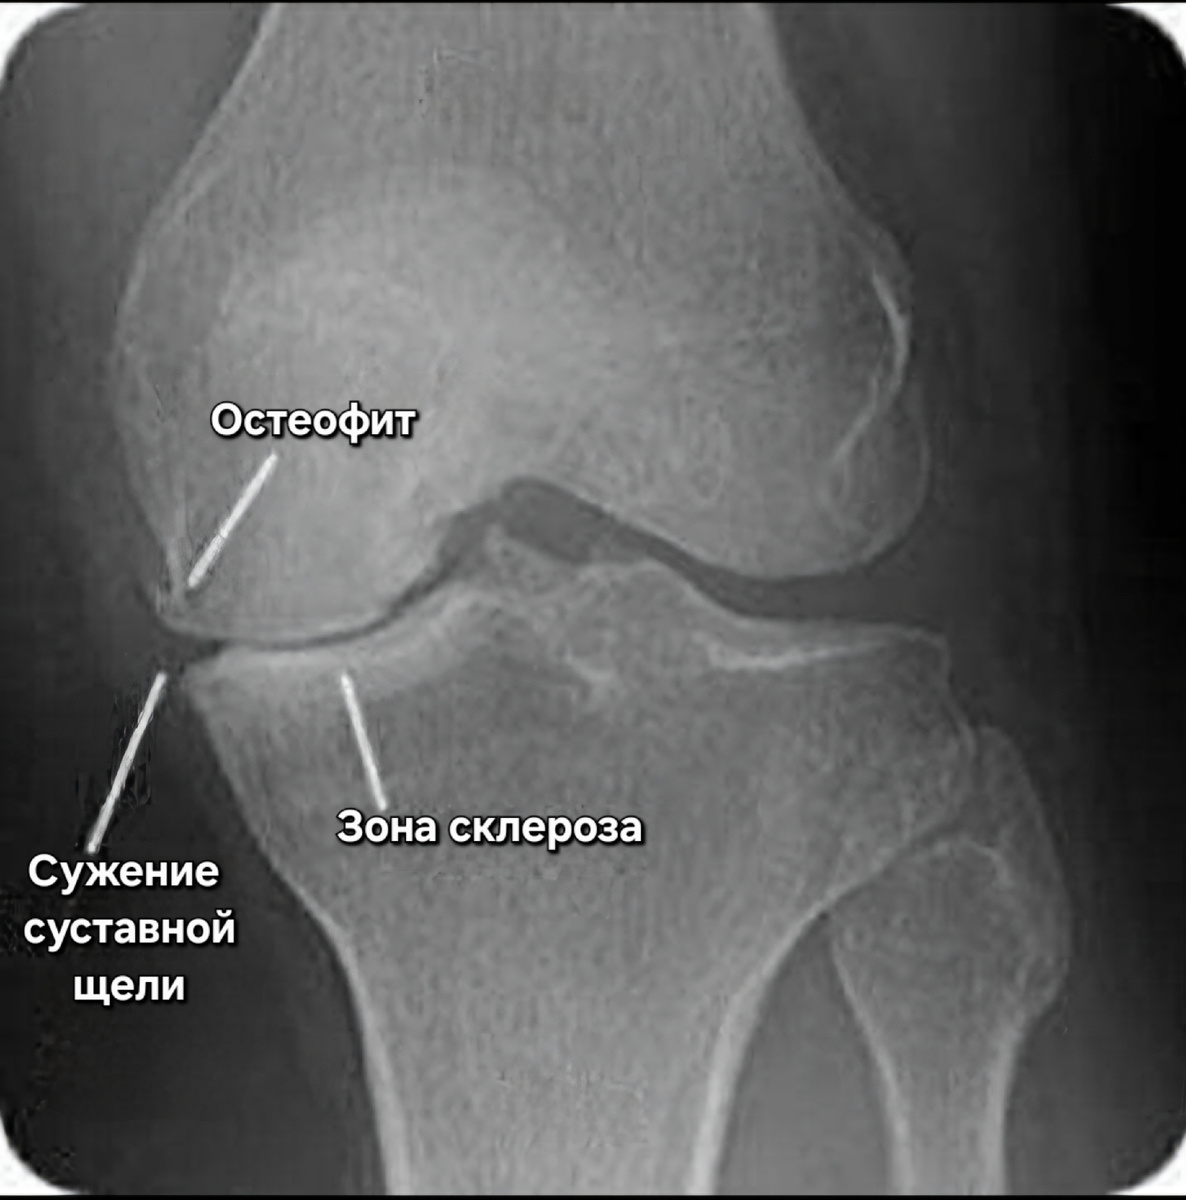

Рентгенологические признаки артроза коленного сустава https://pin.it/2JjBd8yLu

• Рентгенография коленного сустава - выполняется в прямой и боковой проекциях. Для дополнительной оценки бедренно-надколенникового сочленения используется аксиальная проекция надколенника.

Рентгенография коленного сустава в 3х проекциях. Показаны деформирующие изменения в суставе.